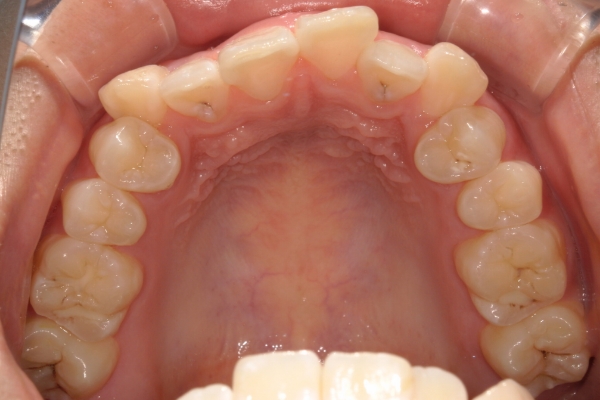

AFTER

治療後

骨格的に下あごが前下方に長いことが原因で、受け口、開咬(前歯が当たらない)の症状がでていました。また下あごが右にずれており、その影響で上下の歯列正中(真ん中)の大きなずれも生じていました。顎変形症手術も選択肢の一つでしたが、患者さまの希望もあり、下顎左側小臼歯の抜歯をして通常の歯列矯正で治療をしました。

前歯、奥歯の噛み合わせが大きく改善され、上下の歯真ん中が一致しました。食べ物が噛みやすくなったこともですが、歯列の見た目が整った点にも患者さまは満足されていました。